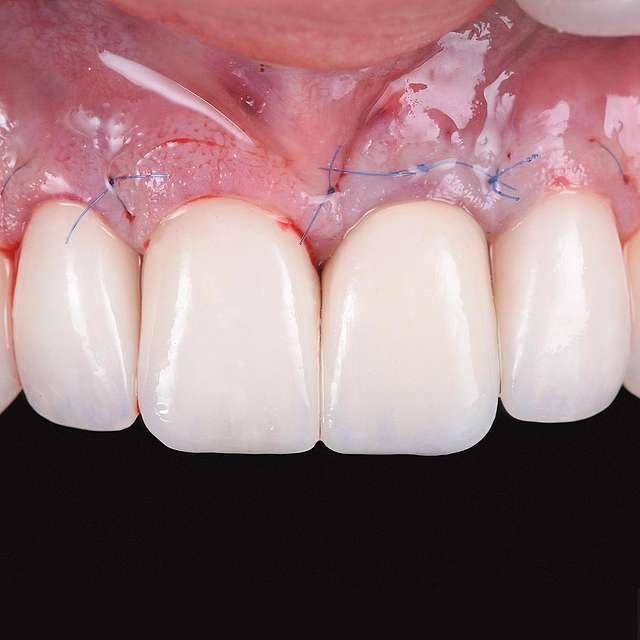

Grefa gingivala este o micro-chirurgie prin care se transplanteaza o mica bucata de tesut moale - gingie sau tesut conjuctiv (stratul intern al gingiei) pentru a acoperi un defect gingival. De obicei, acest tip de interventie este necesar pentru augmentarea implanturilor dentare, sau pentru a acoperi defecte cauzate de traume sau de afectiuni parodontale.Grefele se recolteaza din zona molarului de minte, sau de pe palat, si sunt transplantate in zona afectata.

Acesta interventie este una foarte delicata, lamele folosite pentru a efectua procedura sunt aceleasi folosite in oftalmologie, iar firele de sutura sunt si ele foarte fine. Firele se indeparteaza dupa 7-14 zile, in functie de caz, cand are loc vindecarea primara. Maturarea grefei dureaza aproximativ 90 zile, de aceea in momentul inserarii implanturilor preferam sa facem si grefa de tesut, pentru a sincroniza timpii de vindecare si ambelor proceduri.